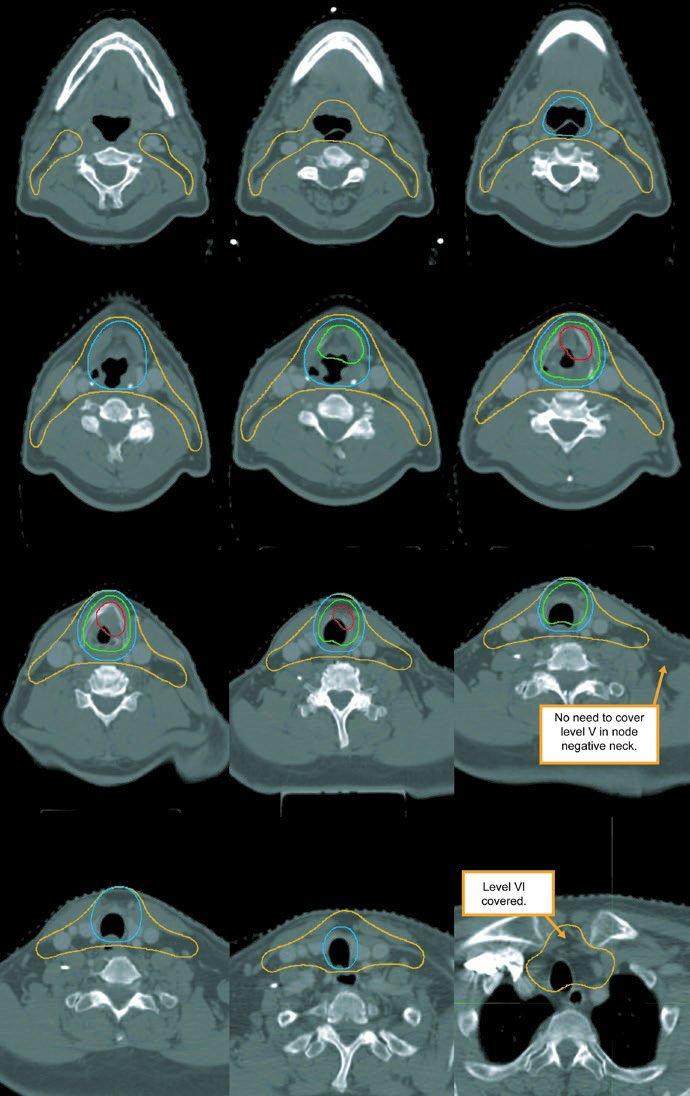

The subclinical primary CTV should cover the whole larynx from the bottom of the thyroid notch to the first tracheal ring, or farther inferiorly when needed. The subclinical nodal CTV should include at least levels II-IV and, in many cases, level VI. In the elective node-negative neck, the superior extent of level II stops where the posterior belly of the digastric crosses the internal jugular vein, corresponding to the caudal edge of the lateral process of C1. In the node-positive neck, level II should extend to the skull base and include the ipsilateral retrostyloid nodes.

| CTV 54-60a | Should encompass the entire GTV. Includes the entire larynx, from the bottom of the hyoid or the top of the thyroid notch to the bottom of the cricoid cartilage, with further inferior extension when needed. High-risk nodal regions include levels II-IV and the retrostyloid space on the involved node-positive neck. In the node-positive neck, level II should be treated to the base of skull. Level VI should be included if there is subglottic extension or a trach. |

| CTV 54b | Levels II-IV of the uninvolved neck. In the node-negative neck, the superior border of level II stops where the posterior belly of the digastric crosses the internal jugular vein, or at the caudal edge of the lateral process of C1. Levels IB and V are not included unless there is gross disease at those levels. Retropharyngeal nodes may be covered at physician discretion on the side of bulky adenopathy because of retrograde flow. Level VII coverage is recommended for subglottic extension or hypopharyngeal involvement. |

Levels IB and V are not elective by default and are only included when gross disease is present there. Retropharyngeal nodes may be covered on the side of bulky adenopathy at physician discretion. Level VII is recommended for subglottic extension or hypopharyngeal involvement. That is one of the most useful parts of the chapter because it turns abstract spread patterns into concrete cranial and caudal borders.

The figure caption adds two good reminders. In that example, level IB was included by the treating physician even though it can be omitted. The upper trachea was not treated, but the text notes that it should be included when indicated. That is a useful warning against copying a figure without rechecking the anatomy.